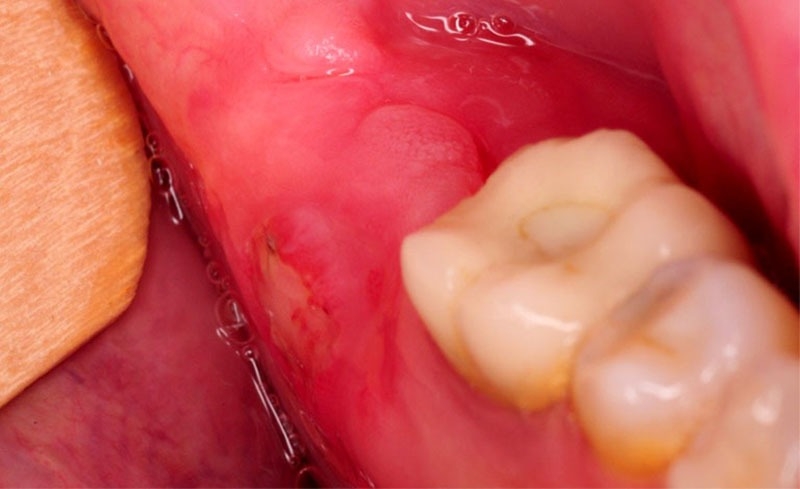

Các túi mủ xuất hiện tại vùng chân chân răng, là nơi tập trung của vi khuẩn và gây ra mùi hôi khó chịu. Tình trạng này có thể gây ảnh hưởng đến cảm giác vị giác và gây đắng miệng. Ngoài ra, nó cũng có thể tiềm ẩn nguy cơ gây tổn thương đến hệ thống nha chu bên dưới.